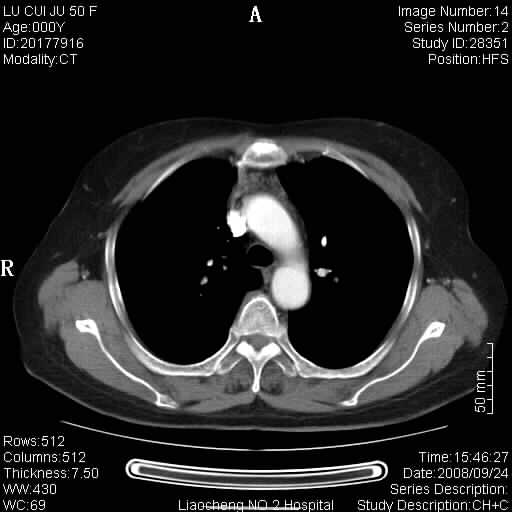

标题: CT15870:F50Y,纵膈占位,是不是胸腺瘤,请各位高手讨论。

临床表现为重症肌无力;ct增强扫描可见前纵膈胸腺部位弥漫性簇状软组织节结灶,不知道是不是胸腺瘤,请各位高手讨论。

胸腺外缘稍向外突,未见确切占位改变。结合临床考虑胸腺增生可能性大。